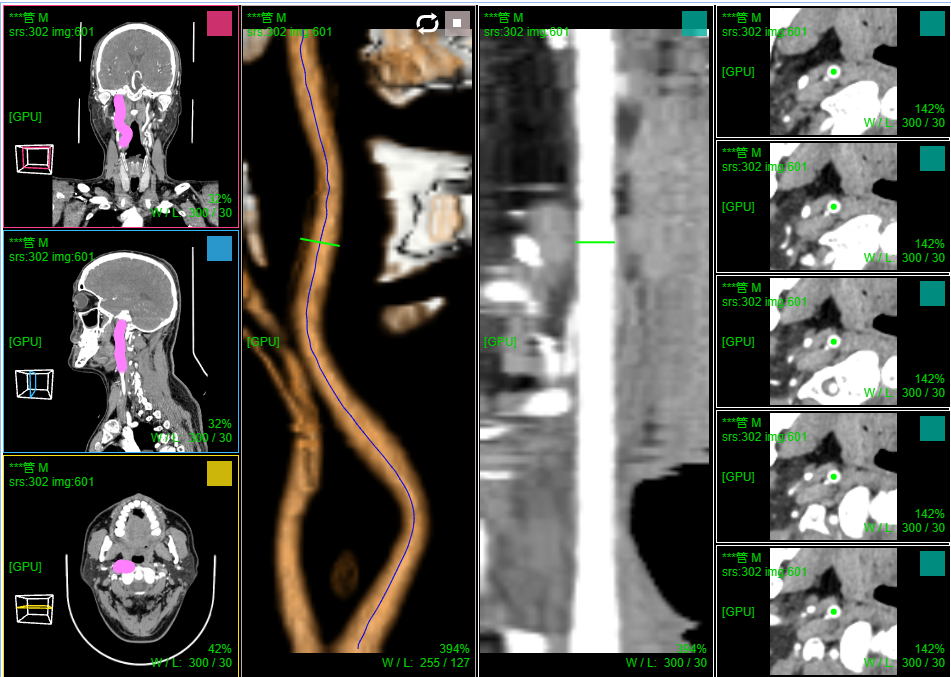

十、血管CPR曲面拉伸拉直

三维:MPR多平面重建(支持任意旋转)、CPR任意曲线切面重建、MIP最大密度、VR容积重建、VE虚拟内窥;任意三维裁剪、一键去床、一键去头骨、快速旋转、厚切MPR(最大密度/最小密度/均值/VR); 手工/半自动分割,分割目标三维渲染; 肋骨CPR拉伸渲染、牙神经管渲染、血管CPR拉直渲染等

CPR曲面重建 、厚切曲面;